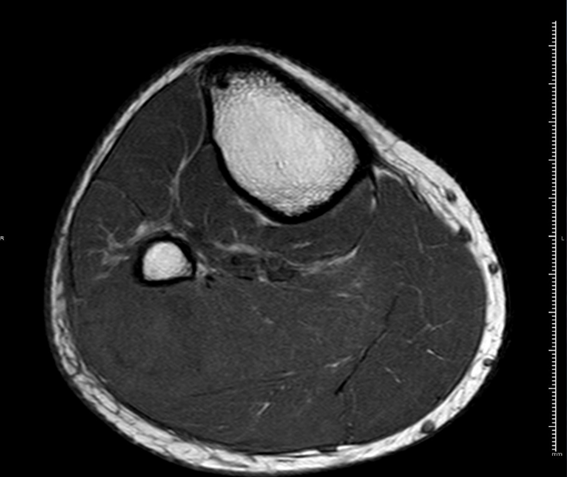

RM Pierna Derecha. Secuencia T1, corte axial.